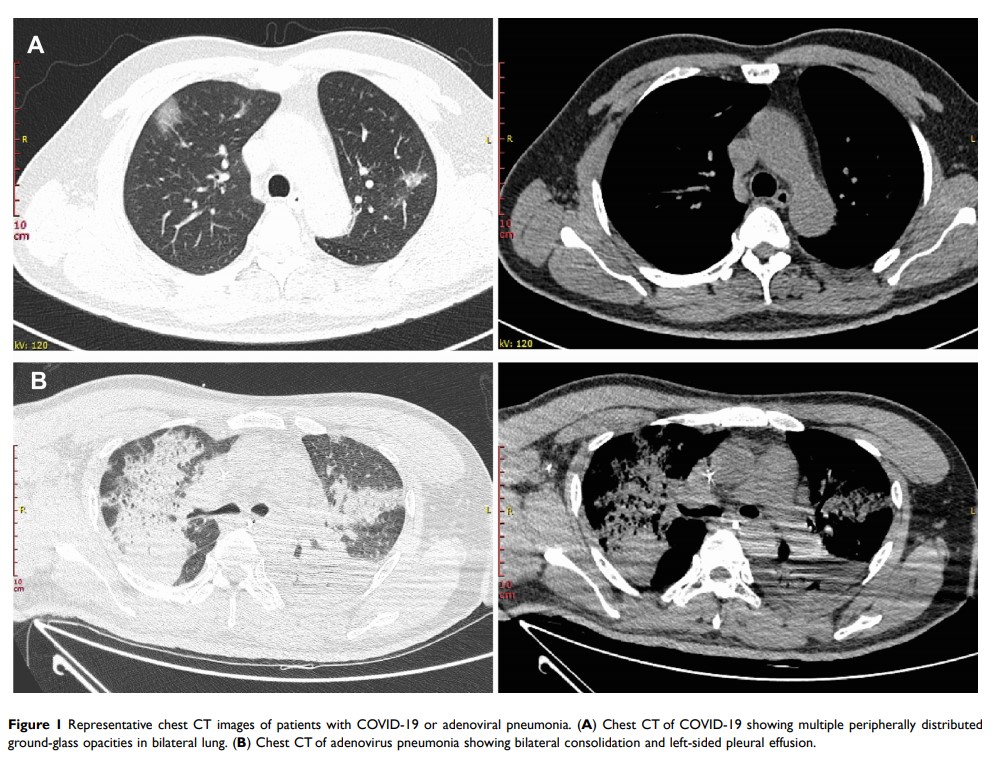

比较 COVID-19 和腺病毒性肺炎的临床、实验室和放射学特征:回顾性研究